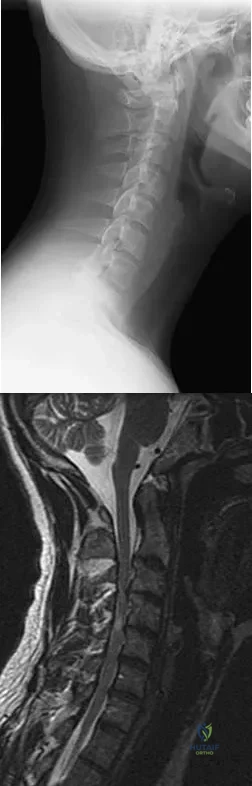

Question 57

Figures 25a and 25b show the radiograph and MRI scan of a 48-year-old man who reports increasing unsteadiness in his gait and hand clumsiness. Examination reveals a positive Hoffmann's reflex bilaterally, positive clonus, and a spastic gait. Management should consist of

Explanation